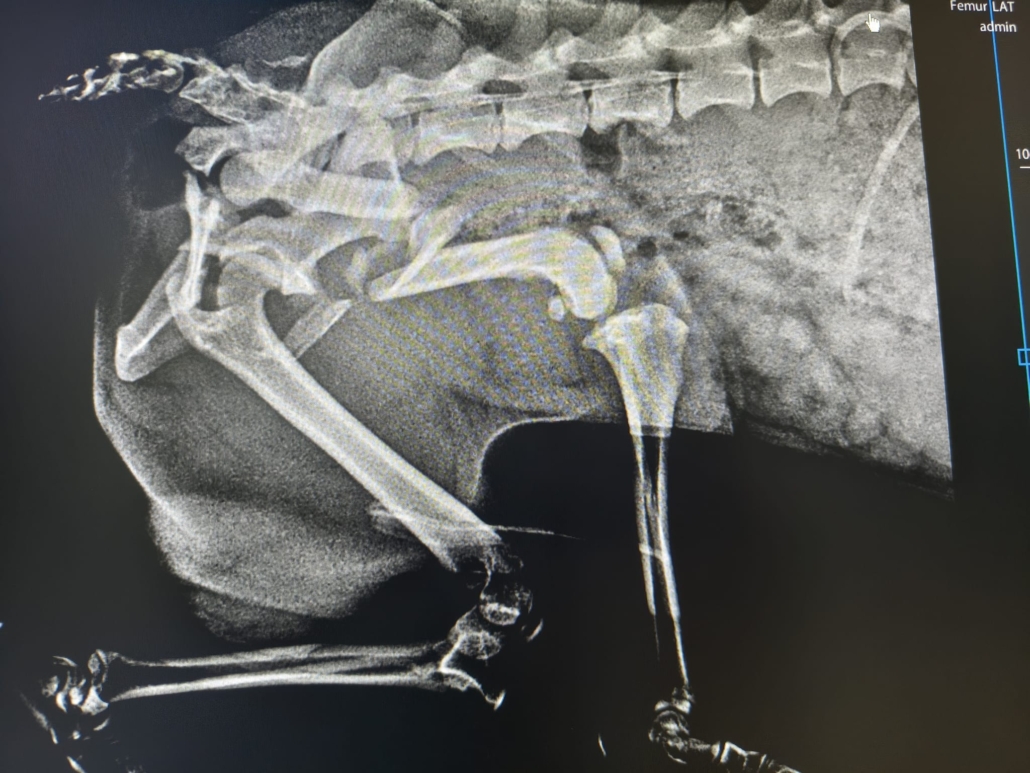

leider war sein Name durch den Umstand entstanden, dass er verletzt (vermutlich durch einen Unfall) auf der Straße gefunden wurde….

Wie lange er schon mit dieser Verletzung unterwegs war…. wir wissen es nicht… auch über sein bisheriges Leben können wir nichts sagen…

Er hat die OP gut überstanden und darf sich noch ein bisschen in der Tierarztpraxis erholen… doch dann braucht er einen sicheren Platz um wieder vollkommen zu genesen…. Leider ist es fast unmöglich vor Ort eine Pflegestelle zu finden… 🙁 und die Finderin, die sich aktuell um ihn kümmert, verlässt im März Rumänien…